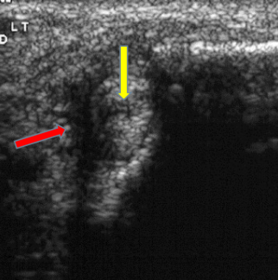

| What does the red arrow show? What does the yellow arrow show? | Red arrow = fluid Yellow arrow = tendon tear |